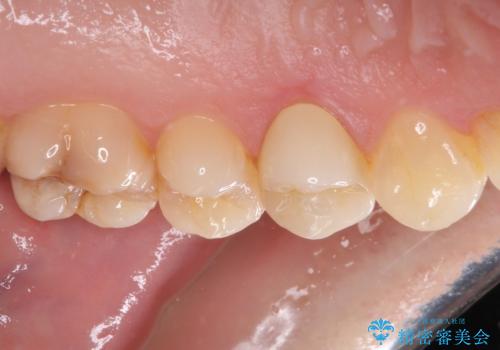

根管治療を行った奥歯は、再発防止や残された歯質を守るため、クラウンによる補綴治療が必要となります。

補綴後6ヶ月経過しレントゲンを撮影したところ、根尖周辺の病変が消失していることが確認できました。